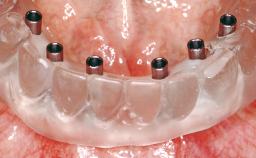

An 83-year-old male patient requested treatment for his existing maxillary complete overdenture and mandibular complete denture. He reported no general medical conditions of significance that would affect his dental treatment and was taking no prescription medication. He denied suffering from oral pain and displayed no evidence of parafunctional habits or temporomandibular joint disorder. Oral and radiographic evaluation revealed two retained maxillary teeth (13 and 15) supporting prefabricated ballshaped attachments. Both teeth were mobile and associated with active periodontal disease and extensive dental caries; these were considered non-restorable and were recommended for extraction. The patient’s existing complete maxillary and mandibular prostheses were approximately 2 years old. He was very satisfied with the appearance of both prostheses. His chief complaint was related to the instability and lack of retention associated with the existing mandibular prosthesis.

# of Implants | 2 |

Prosthesis Type | RDP |